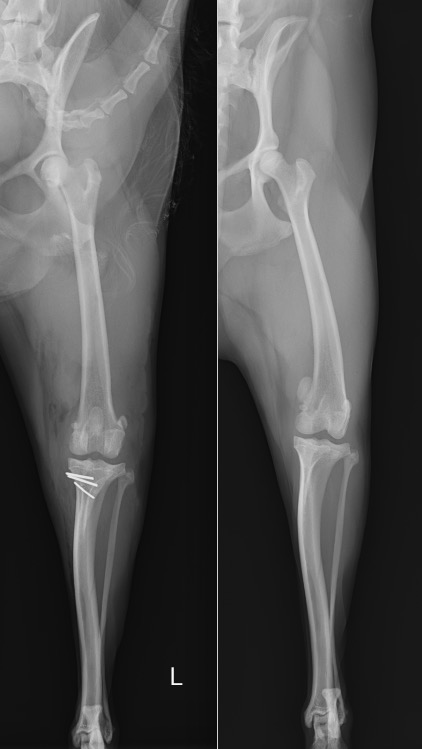

術前・術後のX線を見比べると、膝蓋骨が真ん中に整復されていることが分かります。

白く見えるのはステンレス製のピンであり、脛骨粗面転移という手技を行ったために使っています。

左後肢 【左:術後 / 右:術前】